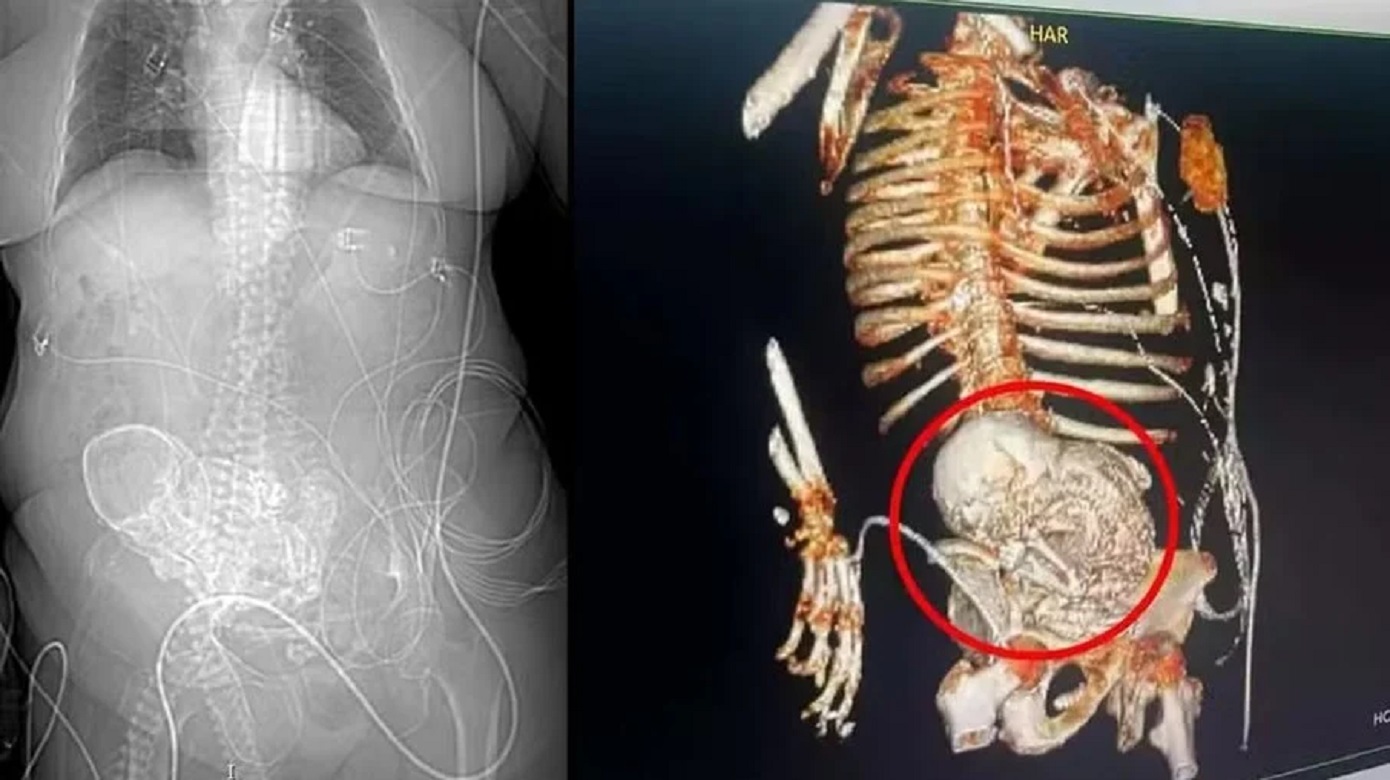

Caso raríssimo

Idosa de 81 anos carregou ‘bebê de pedra’ no ventre por mais de 50 anos, no MS

A situação aconteceu no dia 14 de março deste ano, quando uma tomografia revelou a presença do feto calcificado em seu abdômen